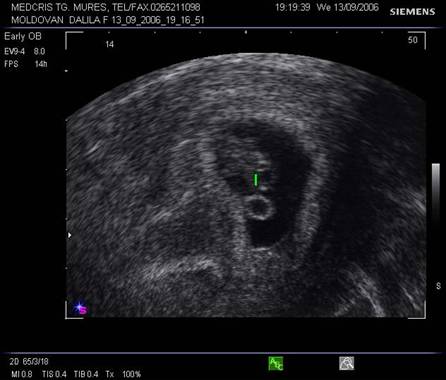

Fig. nr.19. Vezicula telencefalica la 9 sapt

( zona anecogena marcata cu linie )